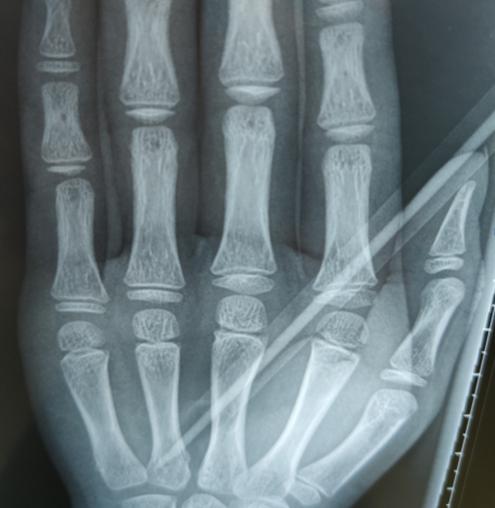

淼淼的妈妈和老师带着淼淼下午两点多才赶到我院,接诊的手外科三病区的李刚医生发现,铅笔斜着刺进淼淼的掌心2厘米,万幸的是没有造成“贯穿伤”。

李刚医生手术团队立刻为淼淼进行了手术,术中探查见其血管、神经、肌腱已经部分损伤了。手术团队延长切口,谨慎取出铅笔,在显微镜下修复损伤的血管、神经和肌腱,并打上石膏。